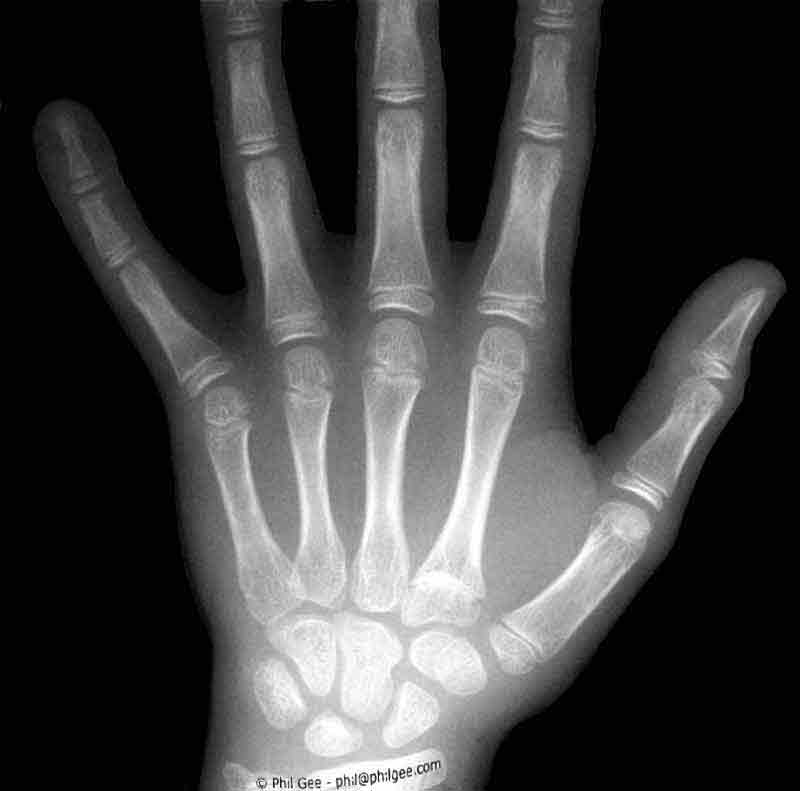

Medical Radiography

The resulting image is a 'negative' in the conventional sense where the dark areas represent maximum exposure the white areas minimum and the grays proportional amounts dependent upon the density, opacity, refractivity of the subject and the amount of exposure given.

However modern day X-ray techniques use digital imaging with the plate image being displayed on a digital monitor.

In a CT scan ( Computed tomography ) a three dimensional image is computed from a series of X-ray images of 'slices' through the object under investigation